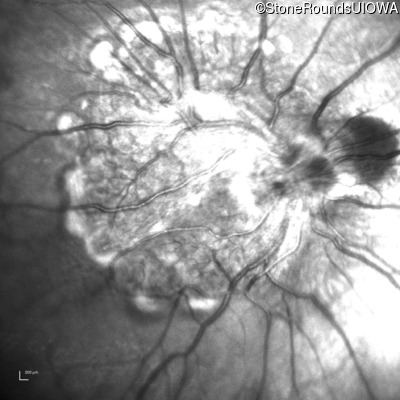

This 9 year old male was noted to have some crossing of his eyes at 2 months of age and the eye exam which followed identified a retinal lesion in the right eye. When he was six years old an epiretinal membrane was noted in his left eye. Two years later it was decided that it was a thin hamartoma in that eye as well. He underwent neuroimaging at age 7 which identified bilateral acoustic neuromas.

| Age at visit: 8 years |

| Age at visit: 10 years |

| Age at visit: 11 years |

| Age at visit: 14 years |